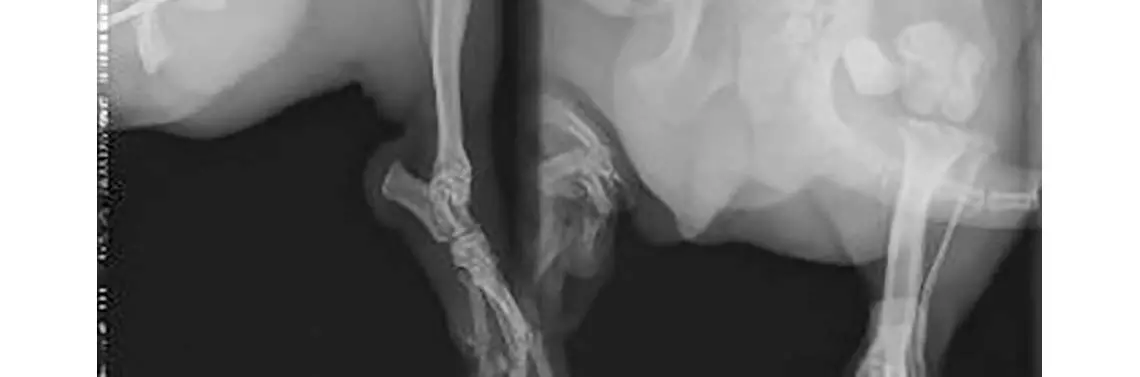

W innym zakładzie leczenia zwierząt wykonano zabieg osteosyntezy za pomocą pojedynczego gwoździa śródszpikowego. Osiem dni po zabiegu wykonano kontrolne zdjęcie rentgenograficzne (RTG) (fot. 2), które uwidoczniło brak stabilizacji odłamów, destabilizację oraz rotację odłamu dalszego.

RTG boczne i strzałkowe po zabiegu osteosyntezy na gwóźdź śródszpikowy